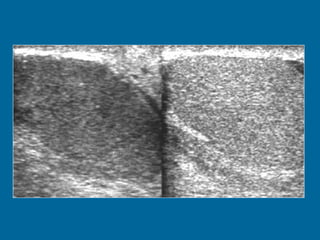

Transverse US scan of the testis shows a normal transmediastinal artery (arrow) as a linear hypoechoic band. Color Doppler flow US (not shown) revealed flow through the vessel.

Transverse US scanof the testis shows a normal transmediastinal artery (arrow) as a linear hypoechoic band. Color Doppler flow US (not shown) revealed flow through the vessel.